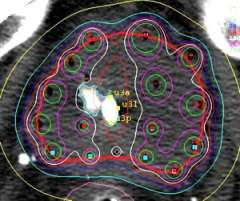

HDR Dose Distribution

This is a transverse view of a typical prostate implant showing the radiation "isodose" levels. The blue dots are the superimposed dwell positions along the 17 catheters. (imagine looking end on at a string of beads).

Notice the central area of reduced dose created by the ability to adjust the time the source spends in the 5 interior catheters to spare the urethra (outlined with yellow dots). Also notice the space between the implant and the rectal points. In its natural position, the prostate lies on top of the anterior rectum, separated by a thin layer of tissue, called fascia. The non-fixed template technique allows the physician to slightly lift the prostate away from the rectum, reducing rectal dose. The HDR system allows for dose adjustments and the treatment is delivered in minutes while the rectum is empty. These advantages over permanent seeding are the reasons why the leading centers that perform HDR implants are all reporting very low, if any, rectal complications. Permanent seeds can shift from their original ideal positions resulting in the actual dose distribution not being like the approved pre-plan. With the HDR system, the prostate is held in position by the catheters and the catheters are held in position by the template. If the patient moves, the implant moves with him. HDR is the most accurate method of radiation dose delivery available.